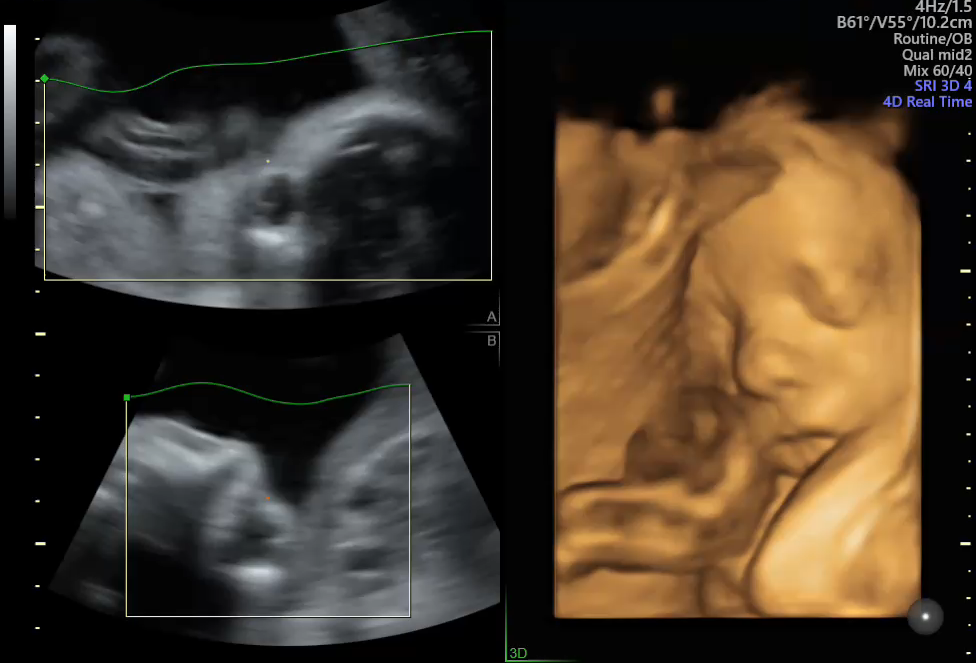

胎儿四维成像

也就是4D超声波技术,是目前世界上最先进的彩色超声技术。四维成像技术(4D),能直观、立体显示人体器官的三维结构及动态、实时地观察立体结构,而以往的二维成像技术只能显示人体器官的某一切面。

四维彩超能够对胎儿进行超声检查,立体显示胎儿的手脚、脸、各器官的发育情况,还可以观察到胎儿在母体里的动态,对胎儿畸形,如唇裂、腭裂、骨骼发育异常、心血管畸形等能进行早期诊断。